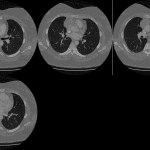

- Smoothly marginated soft tissue mass adjacent to the right heart border, likely in the anterior mediastinum

- Anterior mediastinal mass (thymoma)

- CT was obtained and showed an anterior mediastinal mass that turned out to be a thymoma

- The boundaries of the anterior mediastinum include the right and left heart borders and ascending aorta. Therefore, bulging of these contours can be seen with an anterior mediastinal mass

- Consider the following when you see an anterior (prevascular) mediastinal mass:

- Thymic pathology – thymoma, carcinoma, cyst

- Enlarged lymph nodes – e.g. lymphoma

- Germ cell tumor

- Thyroid enlargement/mass